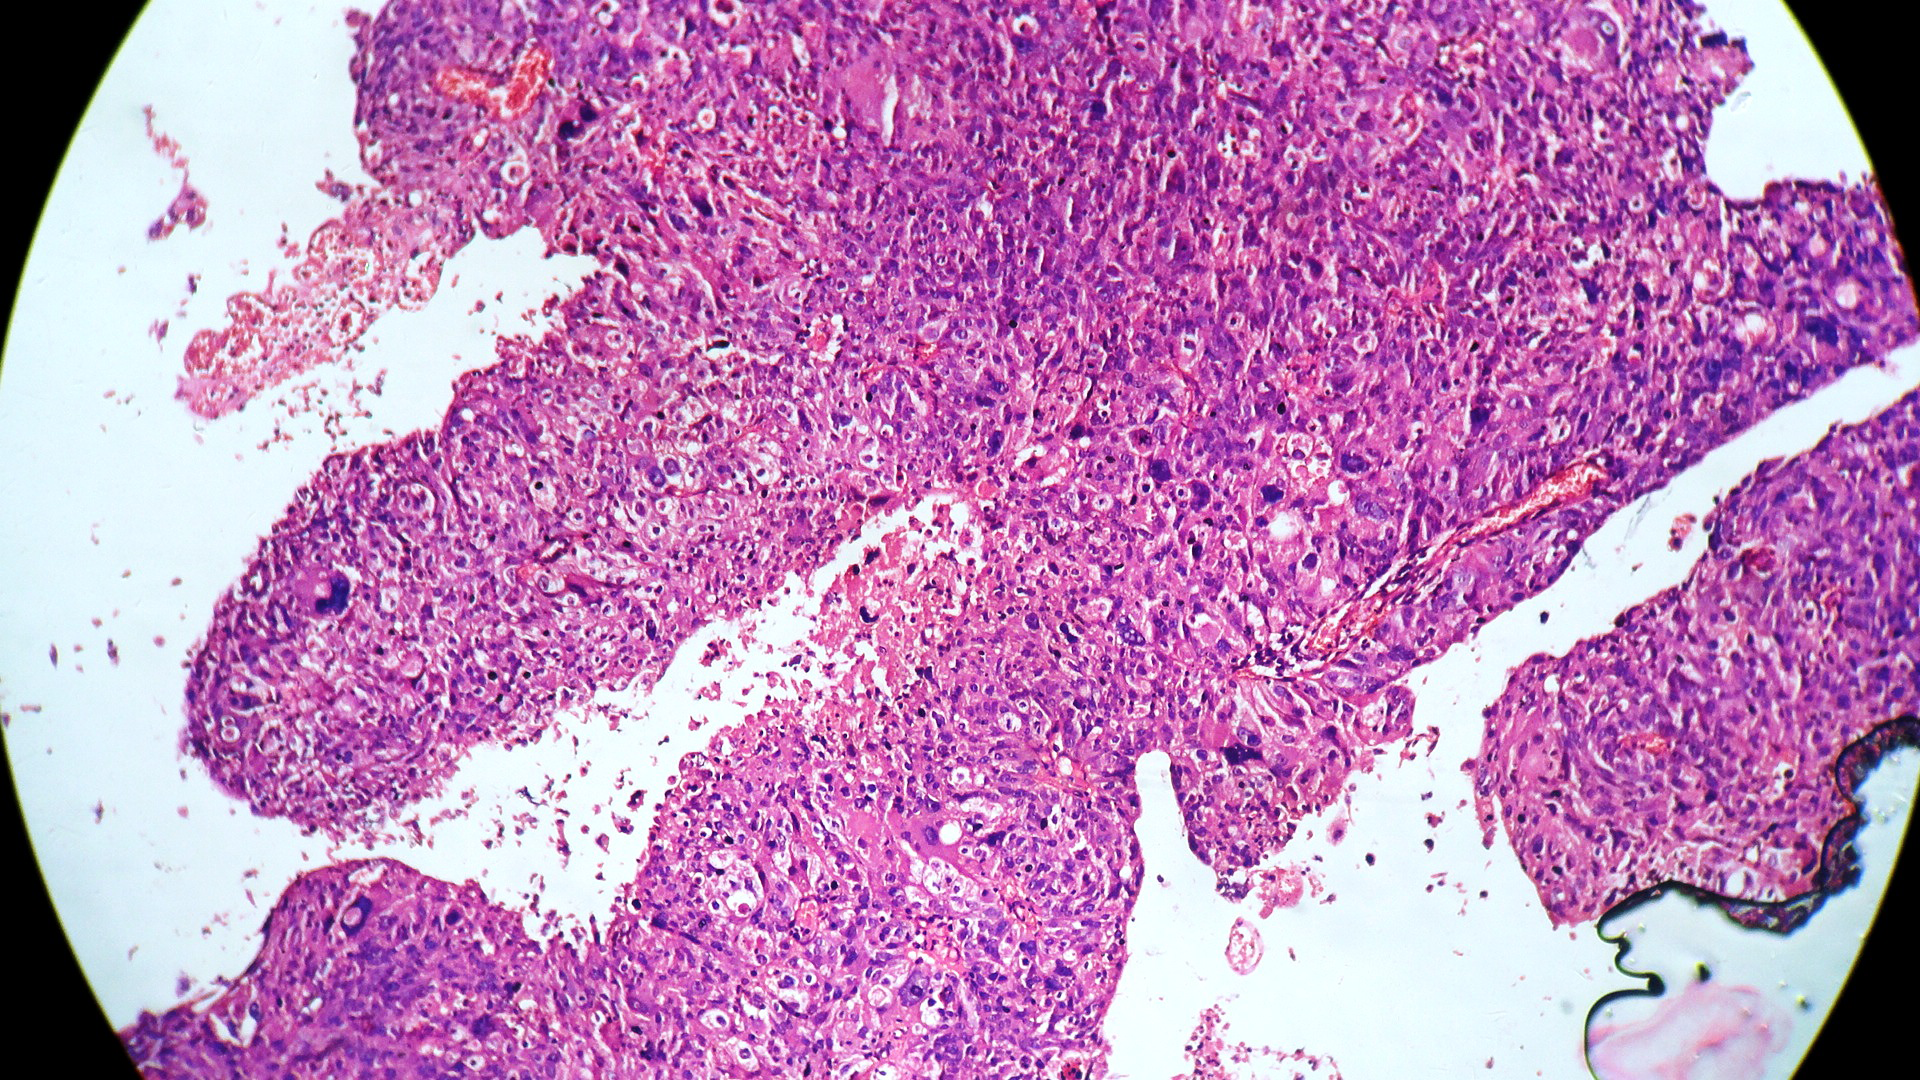

In our study, we made an attempt to evaluate the pattern of tumor growth, its degree of differentiation, progression and associated mucosal changes. In 15 cases of urothelial papilloma, it is characterized by discrete papillary growth with a central fibrovasular core lined by urothelium of normal thickness and cytology (Figure 1). In five cases of Papillary urothelial neoplasm of low grade malignant potential (PUNLMP), histopathologically the tumor is characterized by delicate, orderly, tenuous papillary structures with orderly arrangement of cells within the papillae with minimal architectural abnormalities and nuclear atypia usually limited to basal layer irrespective of cell thickness (Figure 2). The major distinction from papilloma is that in PUNLMP the urothelium is much thicker and nuclei are significantly enlarged. In 21 cases of low grade urothelial carcinoma, histologically it is characterized with papillary axes which are more compact, crowded, fused at the base and lined by unordered cells showing both architectural and cytological abnormalities with frequent mitosis (Figure 3). In 51 cases of high grade urothelial carcinoma showed fused papillary axes over the large areas resulting in sheets and solid areas. The cells have enlarged, hyperchromatic, pleomorphic nucleus in full thickness of the epithelium with increased atypical mitosis (Figure 4). As per TNM staging used in our study we observed majority of the bladder tumours were invasive accounting for 78.25% (Figure 5 & 6) as compared to non-invasive bladder tumours constituting 21.73% of the cases as shown in table 3.

Figure 5 Stage pT1 showing tumour cells in clusters and singly infiltrating into the lamina propria. (H and E stain, 400X).

Figure 6 Stage pT2 showing tumour cells infiltrating into the detrusor muscle bundles. (H and E stain, 400X).